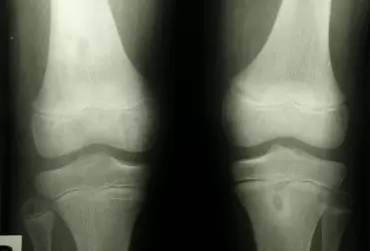

Staw rzepkowo-udowy stanowiący jeden z dwóch stawów tworzących staw kolanowy często jako pierwszy daje objawy podczas tworzących się zmian zwyrodnieniowych. Przenosząc znaczne przeciążenia podczas pracy aparatu wyprostnego kolana narażany jest w dużej mierze na uszkodzenia. Poniżej przedstawiona została grupa schorzeń częściej występujących w przedziale rzepkowo-udowym.